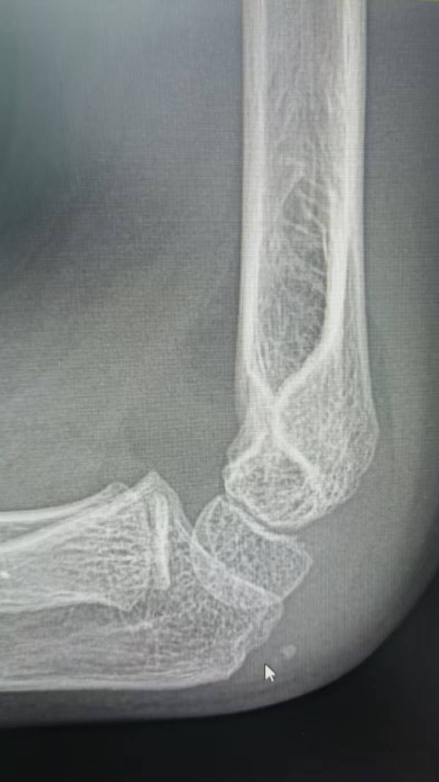

如5岁男童瑞瑞踩着平衡车从广场边缘台阶上摔下,导致左臂肱骨髁上骨折;6岁女童萱萱骑滑板车避让障碍物失去平衡,重重摔倒,造成胫骨骨折。

桡骨远端骨折,通过手法复位